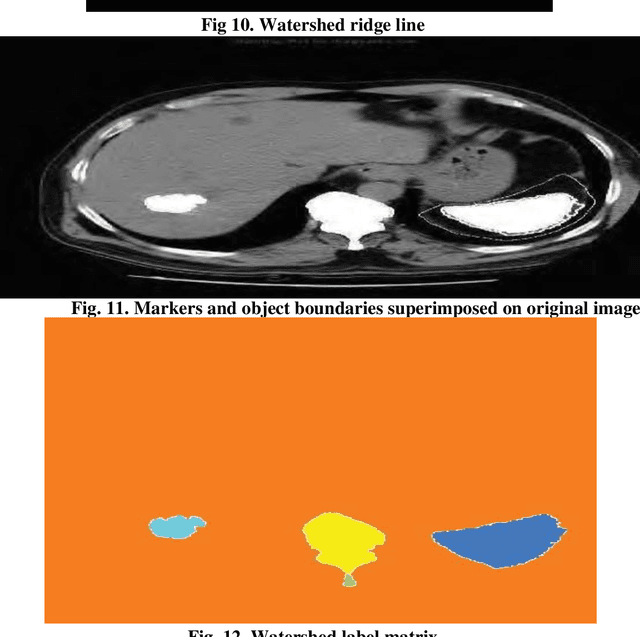

Abstract:Medical imaging is the most important tool for detecting complications in the inner body of medicine. Nowadays, with the development of image processing technology as well as changing the size of photos to higher resolution images in the field of digital medical imaging, there is an efficient and accurate system for segmenting this. Real-world images that for a variety of reasons have poor heterogeneity, noise and contrast are essential. Digital image segmentation in medicine is used for diagnostic and therapeutic analysis, which is very helpful for physicians. In this study, we aim at liver cancer photographs, which aim to more accurately detect the lesion or tumor of the liver because accurate and timely detection of the tumor is very important in the survival and life of the patient.The aim of this paper is to simplify the obnoxious study problems related to the study of MR images. The liver is the second organ most generic involved by metastatic disease being liver cancer one of the prominent causes of death worldwide. Without healthy liver a person cannot survive. It is life threatening disease which is very challenging perceptible for both medical and engineering technologists. Medical image processing is used as a non-invasive method to detect tumours. The chances of survival having liver Tumor highly depends on early detection of Tumor and then classification as cancerous and noncancerous tumours. Image processing techniques for automatic detection of brain are includes pre-processing and enhancement, image segmentation, classification and volume calculation, Poly techniques have been developed for the detection of liver Tumor and different liver toM oR detection algorithms and methodologies utilized for Tumor diagnosis. Novel methodology for the detection and diagnosis of liver Tumor.